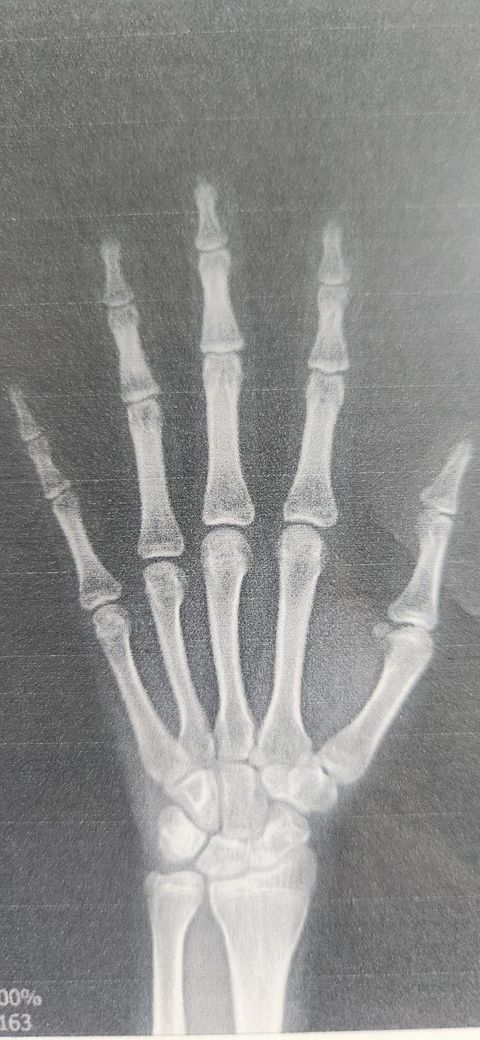

중2 올라가는 남자아이입니다 병원에서 뼈나이 16세라고 3년 빠르다고 했는데 다른분들 보기에도 그런가요? 앞으로 노력해서 잔여키라도 키우려고 하는데 얼마나 더 클수 있을까요?

사진상으로는 "손가락.손목 성장판이 많이 닫혀 보이는 편"이라 병원에서 말한 "뼈

나이 16세 진단이 크게 어긋나 보이진 않습니다."

이 시기엔 "잔여 성장량이 많아도 보통 2-4cm 내외"로 보는 경우가 많아요.

• 제공된 손·손목 X-ray를 기준으로 보면, 전반적인 골성숙은 남아 기준으로 상당히 진행된 상태로 보입니다. 수지의 원위지골과 중위지골, 근위지골의 골단이 대부분 유합되어 있고, 중수골 골단도 성숙 소견이며, 수근골 배열 역시 성인에 가까운 형태입니다. 성장판이 넓게 열려 있는 소아형 소견은 아닙니다. 이 소견만 놓고 보면 병원에서 설명한 “뼈나이 약 16세”라는 평가는 과도해 보이지 않으며, 실제 연령 대비 2년에서 3년 정도 빠른 골성숙으로 해석하는 것이 타당합니다.

남아에서 골연령 16세 전후는 키 성장이 거의 마무리 단계에 해당합니다. 다만 완전한 성장 종료는 아니어서, 현재 성장판 상태에 따라 대략 2cm에서 많아야 4cm 내외의 잔여 성장 가능성이 남아 있을 수 있습니다. 정확한 잔여 키 예측은 키, 부모 키, 성장 속도, 사춘기 진행 단계, 그리고 성장판의 미세한 개폐 상태를 종합해야 하므로 단일 X-ray만으로 단정할 수는 없습니다.

요약하면, 다른 의료진이 보아도 골연령이 많이 앞선 편이라는 판단에는 크게 이견이 없을 가능성이 높고, 앞으로 키는 소폭 더 클 여지는 있으나 큰 폭의 성장은 기대하기 어렵습니다.

중2 올라가는 남자아이인데 뼈 나이가 16세로 판독되었다면, 의학적으로는 성장판이 또래보다 꽤 빨리 성숙된 편에 속합니다. 남자아이의 경우 뼈 나이 16세면 성장판이 거의 막바지 단계라서, 앞으로 키가 크더라도 남아 있는 성장은 보통 2~5cm 내외, 많아도 5~7cm 정도가 현실적인 범위입니다. 생활습관(수면, 영양, 운동)을 잘 관리하면 남은 성장량을 최대한 끌어낼 수는 있지만, 이미 닫혀가는 성장판을 다시 크게 열 수는 없습니다. 지금 단계에서 가장 중요한 건